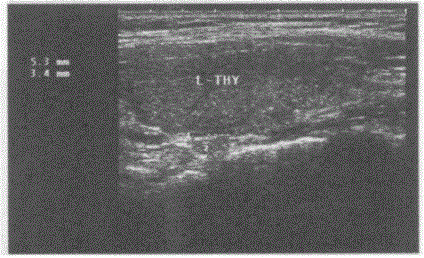

临床资料:男,49岁,常规体检。超声综合描述:甲状腺左叶上、下极后方可见大小均为0.5cm×0.3cm中等回声,边界清晰,形态规则,内回声均匀。 ...

问题 临床资料:男,49岁,常规体检。 超声综合描述:甲状腺左叶上、下极后方可见大小均为0.5cm×0.3cm中等回声,边界清晰,形态规则,内回声均匀。 超声提示:

选项 A.甲状旁腺增生 B.甲状旁腺正常声像图 C.甲状腺旁肿大淋巴结 D.甲状旁腺腺瘤

答案 B